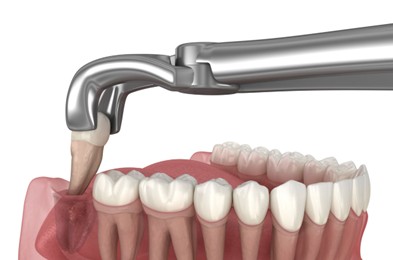

When a wisdom tooth cannot erupt properly or is causing damage to nearby teeth, dentists recommend wisdom tooth extraction Noida or third molar extraction Noida. The procedure may involve either a simple extraction or a minor surgical procedure depending on the position of the tooth. At Dental Lifecare in Sector 71, Noida, the focus is on providing painless removal of third molar Noida using advanced anesthesia techniques and minimally invasive surgical methods. This approach ensures patient comfort, faster healing, and minimal swelling after the procedure.

Patients often worry about the complexity of wisdom tooth surgery Noida, but with an experienced dentist the procedure becomes safe and predictable. Dr. Vijay Prakash Gupta, with 22 years experience, carefully evaluates the tooth position, nerve proximity, and jaw structure before performing third molar extraction Noida. His expertise ensures that patients receive safe treatment with minimal discomfort.